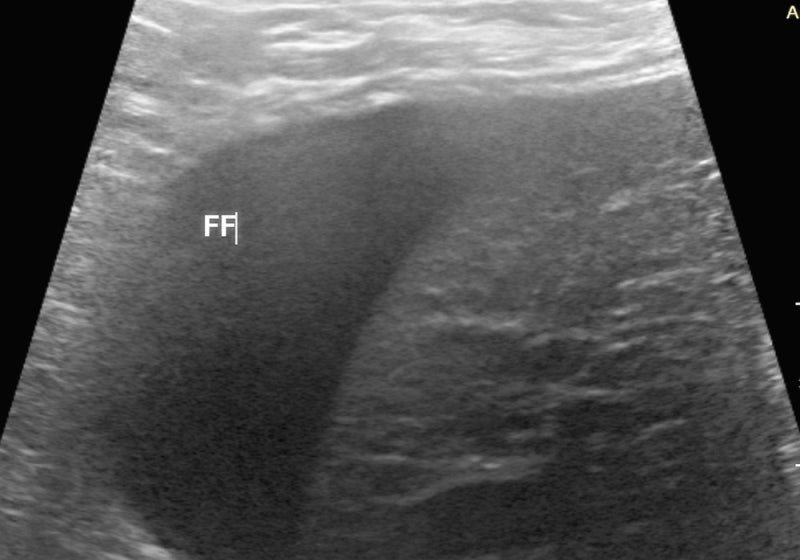

비장파열 (Ruptured spleen)